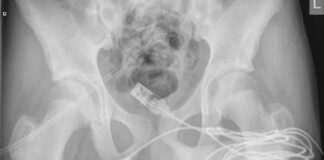

İngiltere’de yaşayan 15 yaşındaki bir çocuğun cinsel tatmin için denediği yöntem...